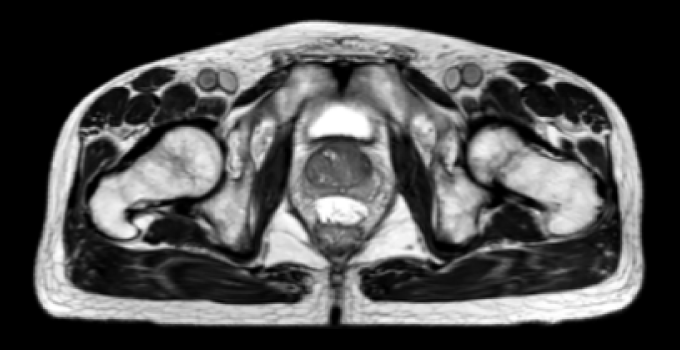

SpaceOAR Vue Hydrogel in different image modalities

T2-weighted Magnetic Resonance images.

T2-weighted Magnetic Resonance images*

*Jeff Michalski, M.D. [2020]. Permission granted by Washington University Image.